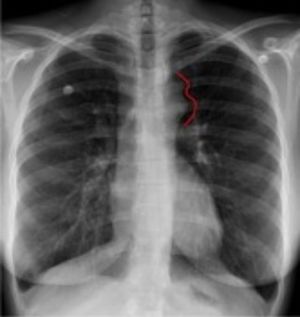

Guess the diagnosis doctorss ?? πŸ€”πŸ€”

Coarctation of the aorta

Its coarctation of aorta

Coarctation of aorta